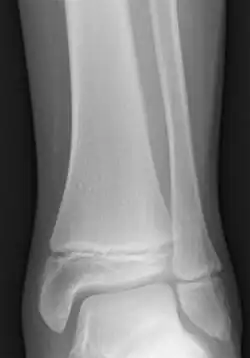

![]() Radiogram of distal tibia (left) and fibula (right) showing two epiphyseal plates | |